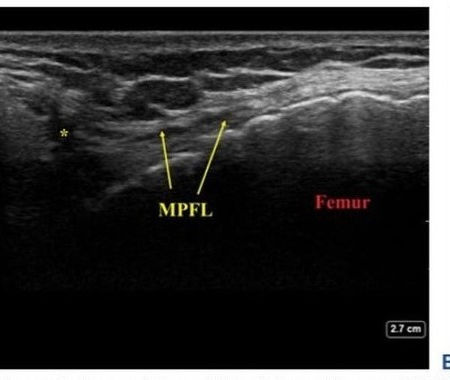

Ultrasound imaging has become a vital tool in the diagnosis and treatment of musculoskeletal disorders, contributing significantly to clinical practice in recent years. This non-invasive method uses a small probe, known as a transducer, to emit high-frequency sound waves that create spatial images of structures like muscles, tendons, joints, and ligaments. The transducer can be moved to capture different angles of the anatomy, providing live imaging, and still photographs when needed.

One of the key advantages of ultrasound over MRI is its ability to allow dynamic assessment, meaning the limb or joint being examined can be moved during the scan. This makes it easier to detect changes in the structure or function of muscles, tendons, and ligaments. Additionally, ultrasound guidance is essential in injection therapies, ensuring that treatments are delivered precisely to the correct location, optimizing outcomes.